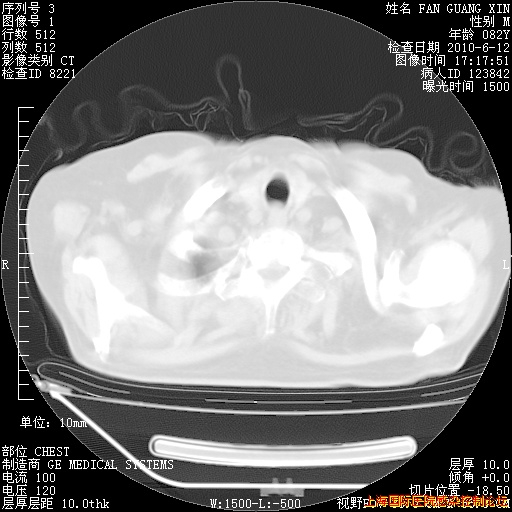

补发6月12日肺部CT肺窗

6月12日肺窗

6月12日纵膈窗